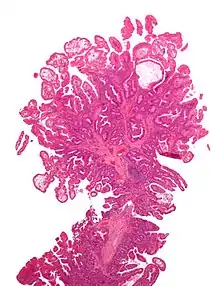

| Tubular adenoma | 2% at 1.5 cm[12] | Low to high grade dysplasia[13] | Over 75% of volume has tubular appearance.[14] | ![]() |

Micrograph of a tubular adenoma, the most common type of dysplastic polyp in the colon

Micrograph of a tubular adenoma – dysplastic epithelium (dark purple) on left of image; normal epithelium (blue) on right. H&E stain.